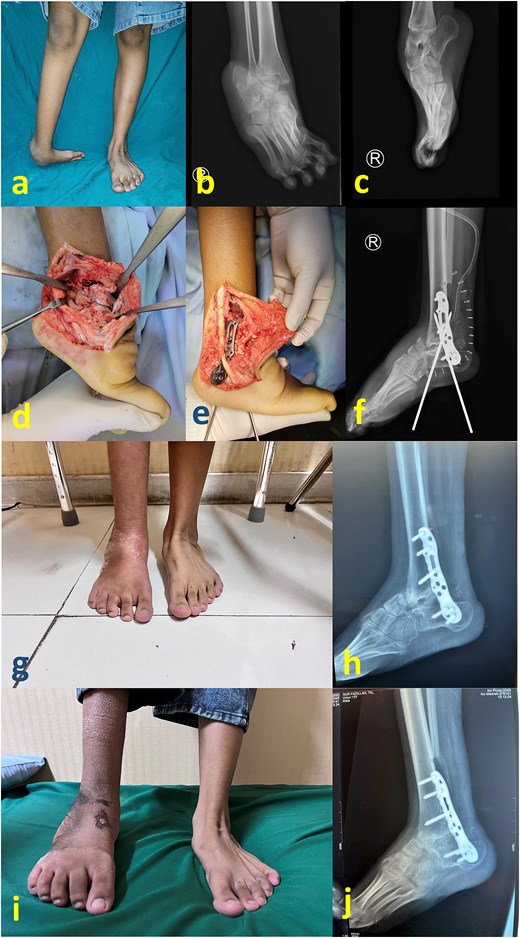

A generally healthy 26-year-old man presented to our clinic complaining of a long-standing deformity of his foot and ankle (Fig. 1a–c). The patient reported that treatment of childhood clubfoot was not acknowledged within his family construct. At the presentation, his main complaint was poor cosmetic appearance, although pain and gait difficulty were present. We decided to undergo single-stage correction with partial talectomy followed by tibiotalocalcaneal arthrodesis using a lateral plate (Agofix, Agomed Medizin-Technik GmbH, Germany). The distal tibia articular surface preparation was done using lateral transfibular approach prior to plate placement.

(a) Preoperative clinical images; (b) and (c) preoperative radiograph; (d) intraoperative image after partial talectomy followed by fixation with plate and screw; (e) immediate postoperative image depicting additional fixation with Schanz screw and external fixator; (f) immediate postoperative radiograph; (g) latest clinical images after 1 year postoperative; (h) and (i) latest radiograph after 1 year postoperative.

The patient was placed in the lateral decubitus position under regional anesthesia. The distal fibula was removed via the lateral transfibular approach. The plantar flexor tendon including the Achilles tendon was initially lengthened, but residual equinus remained due to bony obstruction as well as massive soft tissue contracture. Subsequent axial partial talectomy at the talar dome was performed as much as necessary to facilitate reduction. A lateral tibiotalocalcaneal plate that was applied to firm the ankle (Fig. 1d) was reinforced by a uniplanar external fixator (Fig. 1e and f). First metatarsal dorsal closing wedge osteotomy was completed to address the cavus midfoot. The surgical wound was irrigated and closed in a standard fashion.

An external fixator was worn for 1 month postoperatively and no weight bearing was permitted. Partial weight bearing was permitted 1 month following external fixator removal. The patient was allowed to begin full weight-bearing 2 months postoperatively while undergoing rehabilitation therapy, including proprioceptive exercise. Latest follow-up at 1-year postoperative period showed a stable and plantigrade ankle, with radiological signs of healed arthrodesis (Fig. 1g–i).